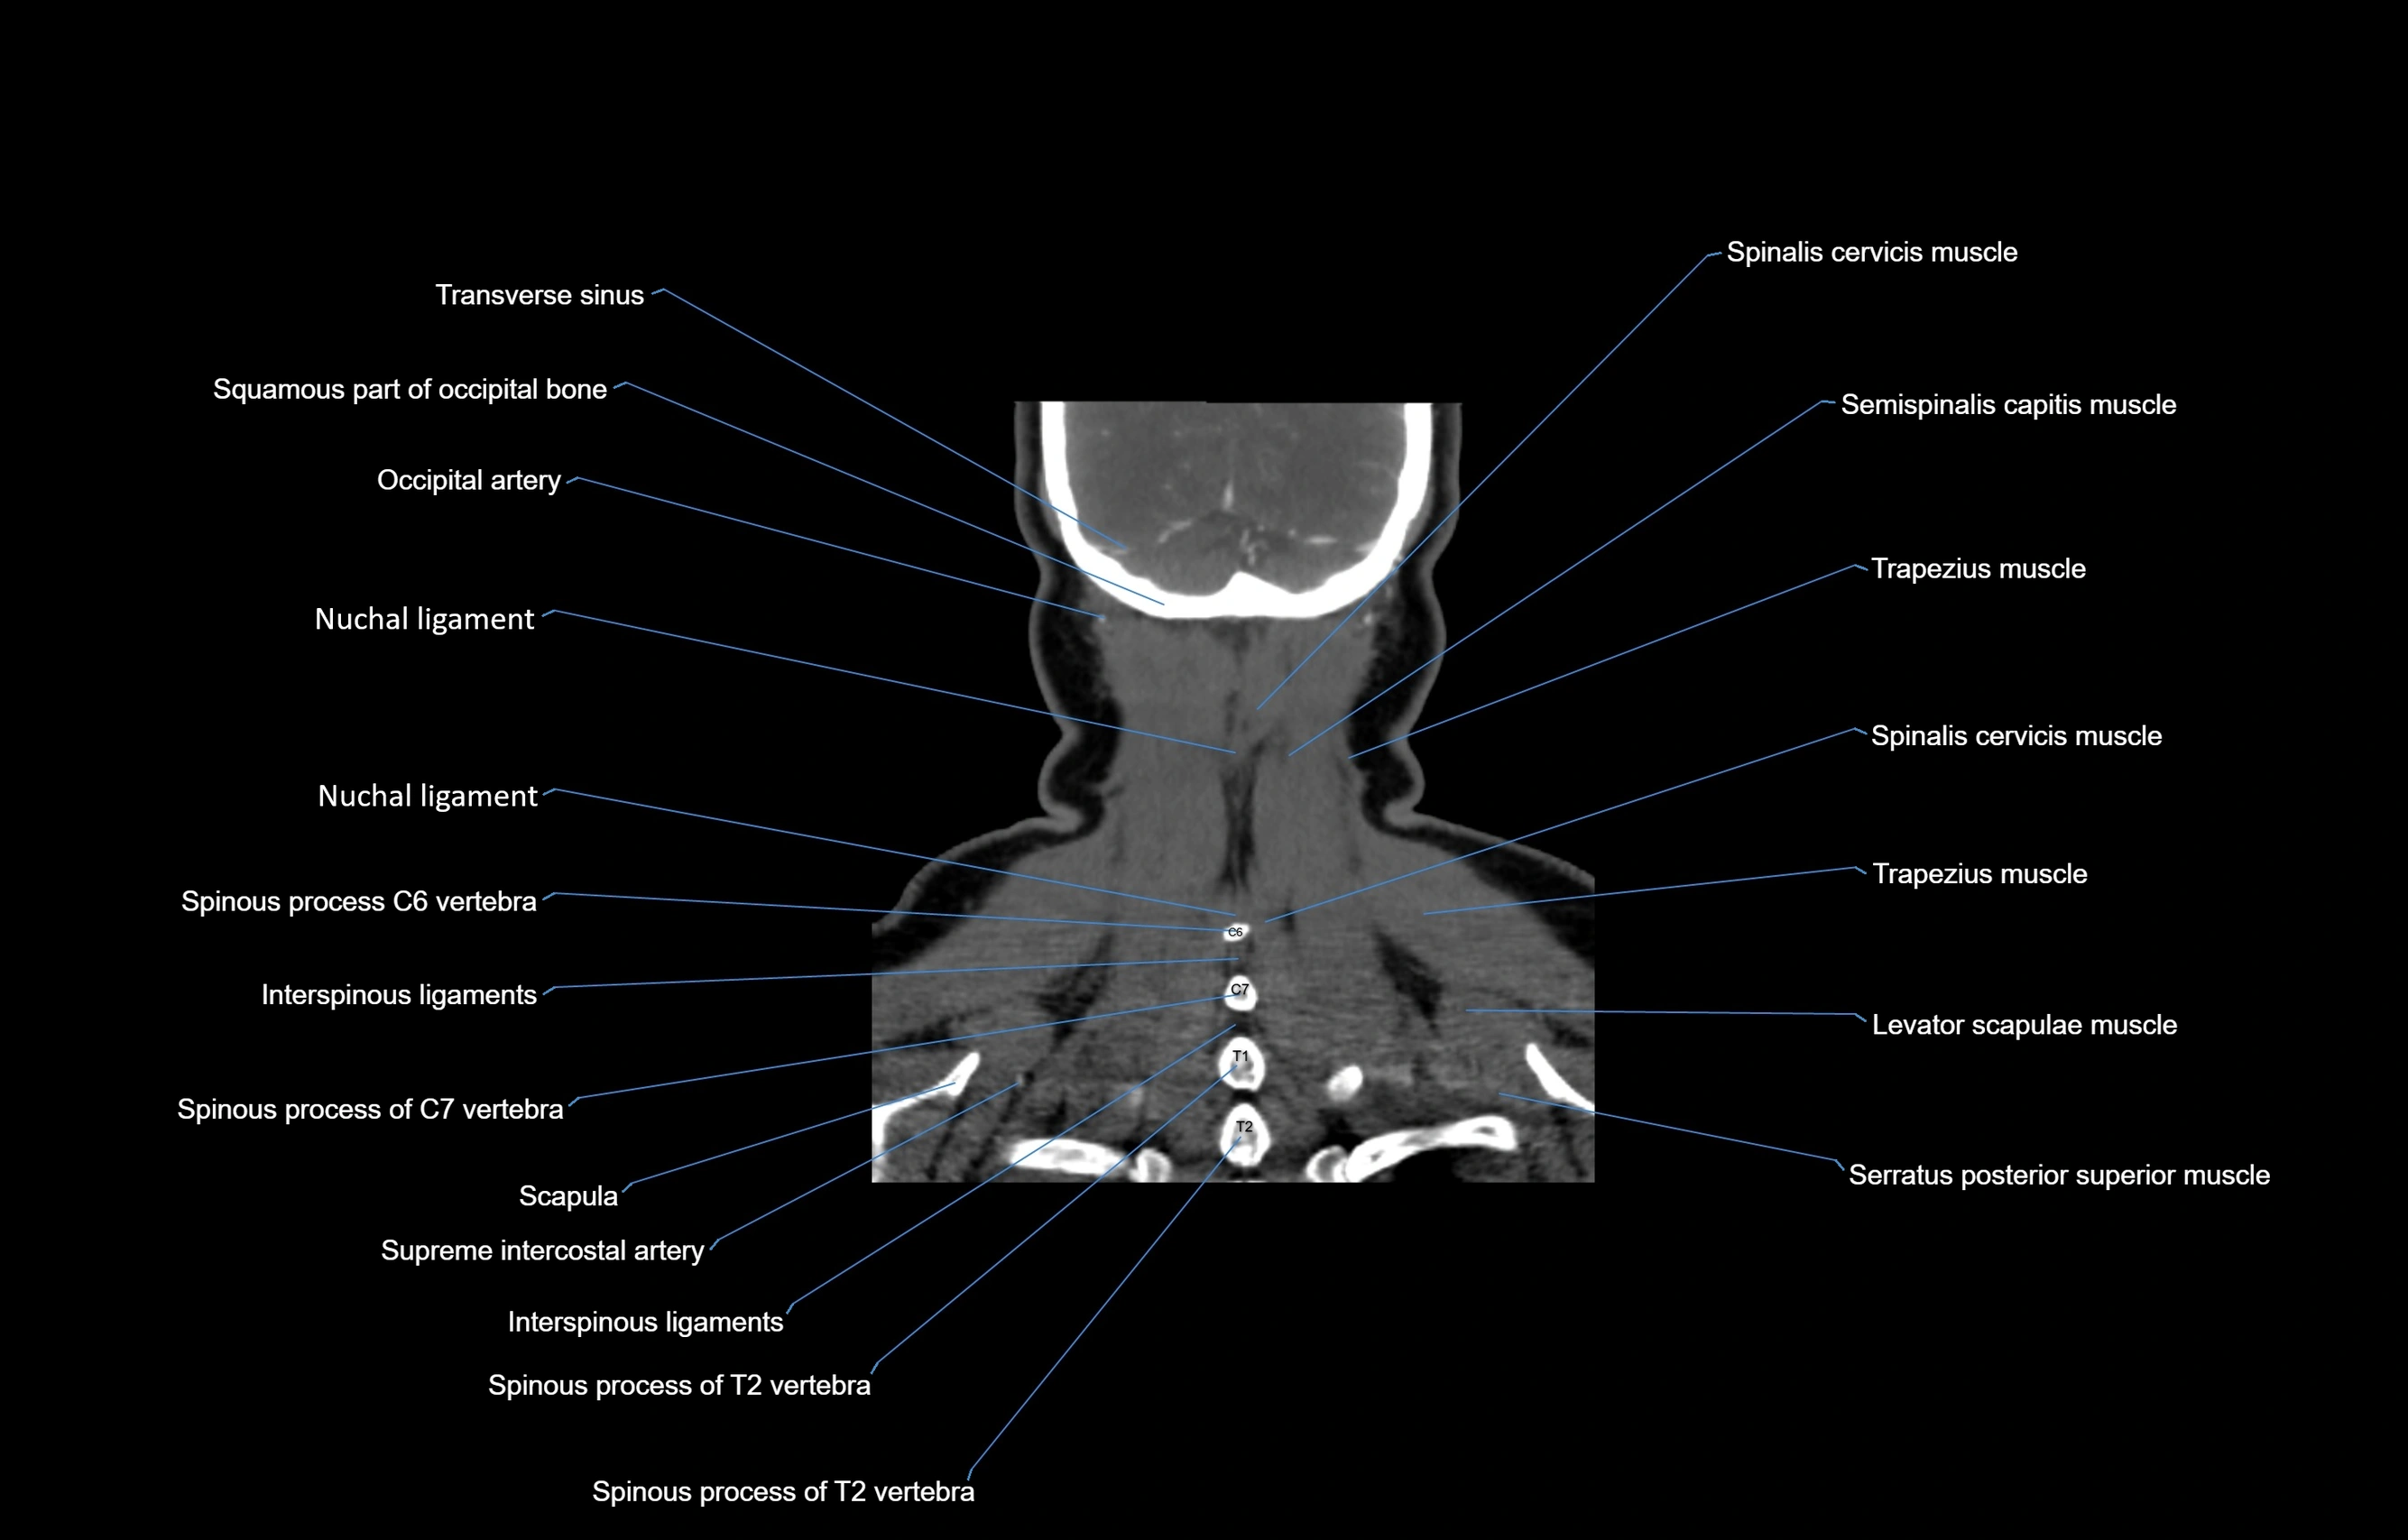

- Nuchal ligament

- Semispinalis cervicis muscle

- Semispinalis capitis muscle

- Spinalis cervicis muscle

- Trapezius muscle

- Levator scapulae muscle

- Serratus posterior superior muscle

- Scapula